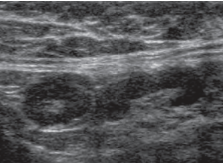

Malignant features:

• *Multiple very hypoechoic nodes**

• *-** Absent hilum/ central necrosis

• Heterogeneous

• *Round**

• >1cm AP diameter

• Taller than wide

Lobulated/ irregular contour

Disorganised vascularity

Differential = mets (calcs)